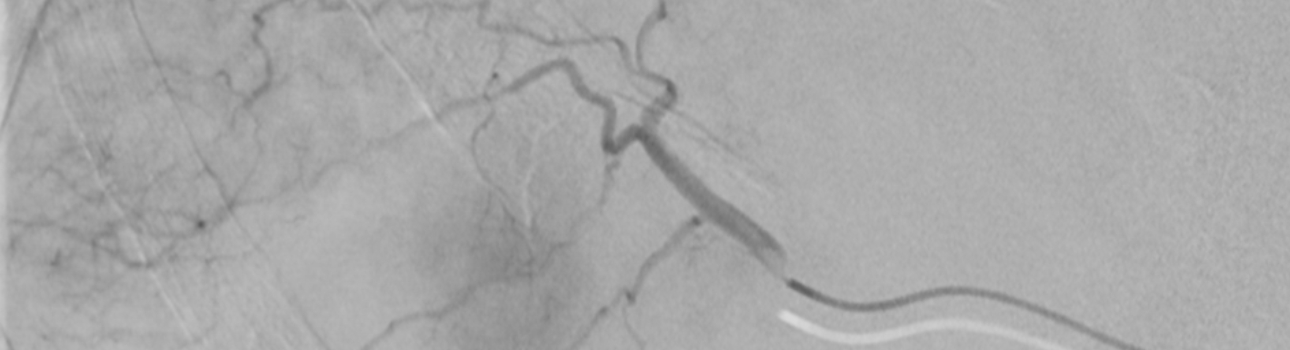

Unter örtlicher Betäubung wird über einen kleinen Schnitt in der Leiste ein Katheter in die Oberschenkelarterie eingeführt. Dieser wird unter Röntgenkontrolle bis in die Leberarterie vorgeschoben. Mit jodhaltigem Kontrastmittel wird die genaue Lage der Tumore bestimmt. Anschließend werden Chemotherapeutika und Embolisationsmaterial in die versorgenden Gefäße injiziert. Dies ermöglicht eine gezielte Verabreichung des Chemotherapeutikums direkt an den Tumor, wodurch die systemischen Nebenwirkungen reduziert werden können, die bei der herkömmlichen intravenösen Verabreichung auftreten können. Gleichzeitig blockiert das Embolisat die Blutversorgung des Tumors, was zu dessen Verkleinerung oder Zerstörung führt.